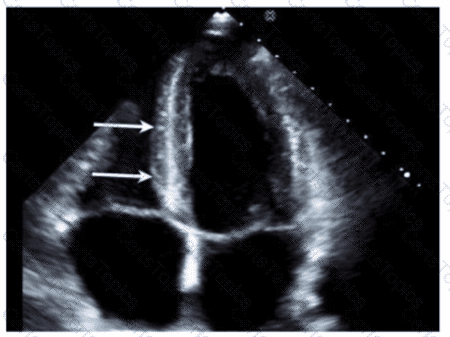

Which wall is indicated by the arrows on this image?

Which condition is most plausible based on the finding indicated by the arrow on this image?